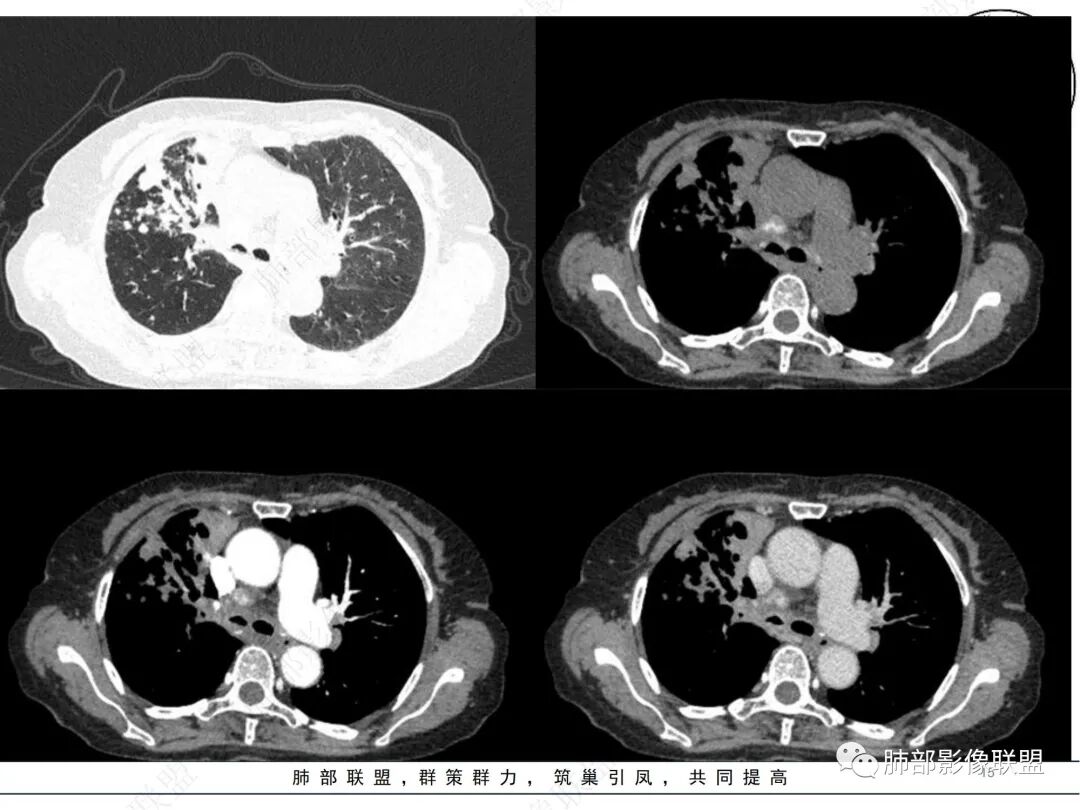

2. CT示右肺上叶多发斑片状实变影,结节影,集群散落,夹杂条索影,边界可分辨,有沿支气管血管束分布趋势,可见树芽征。病灶新旧不等、密度不均。右上叶支气管壁不均匀节段性增厚狹窄,斑点状钙化。纵隔旁部分肺组织含气不良,并显示轻度扩张支气管。病灶邻近胸膜增厚,轻度强化。

4.纵隔多发增大淋巴结,部分融合、钙化。

成簇分布斑片影、结节影、树芽征,边界较清楚,新旧不等,节段性支气管壁增厚伴钙化,管腔狭窄,纵隔及肺门淋巴结增大钙化等都较符合“继发性肺结核、支气管内膜结核”诊断。

继发性肺结核尾随而来的淀粉样变性应当想到,但支气管肺组织淀粉样变性受累及分布范围应当更加广泛、更加弥漫。